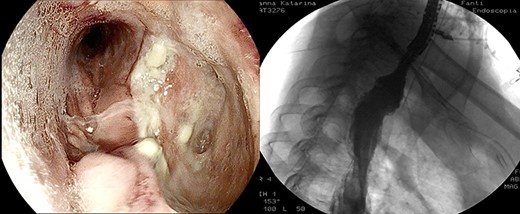

Healthy-appearing granulation tissue and progressive reduction of leak and cavity size.

The patient underwent 14 treatment sessions over 35 days. The leak and the cavity size progressively improved with the development of healthy-appearing granulation tissue s (Fig. 3). Inflammatory indexes and clinical conditions similarly improved. The endoscopic findings were confirmed by CT scans. Complications were not observed.

After the 14th session, the endoscopic evaluation showed a significantly cleaner and smaller cavity (1 cm). Two esophageal fully covered SEMS (Taewoong Niti-S Beta Stent) allowed the patient to have a liquid diet while the leak was safely healing: the stents were subsequently placed and kept for 3 weeks each. Endoscopy and esophagram were performed after SEMS removal, and they demonstrated leak resolution, with a tiny persistent depression at the site (Fig. 4). The patient has not had symptoms of recurrent fistula formation for over 6 months.